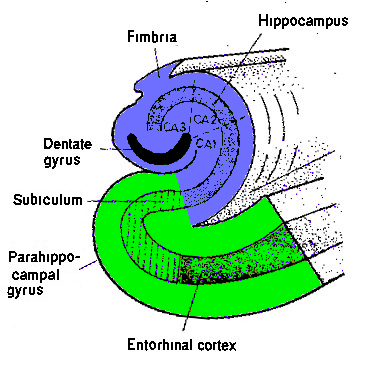

Verlies van de hippocampus leidt tot verlies van het maken van nieuw verbaal geheugen - het geheugen voor dagelijkse handelingen blijft bestaan. Het slachtoffer van het ongeluk kan zich het ongeluk zelf niet meer herinneren, maar het kan wel doorrijden.

De waarnemingen worden hier opgeslagen als complete scenario's, waarvan de onderdelen niet apart toegankelijk zijn - zie de bekende suggestie bij onvindbare herinnering: "Probeer eens om helemaal terug te gaan naar waarmee je begonnen bent". Dit heet het "episodische" geheugen - dat voor automatische handelingen.

En dat de hippocampus aan het begin staat van de vorming van dit soort geheugen is één van de meest vaststaande feiten uit de neurologie, door de ervaringen met patiënt H.M.

Schade aan dit circuit veroorzaakt het verlies van het vermogen tot het maken van nieuw cognitief en verbaal geheugen ("anterograde amnesie"), terwijl het oude geheugen blijft en en het maken van nieuw automatisme-geheugen ("episodisch"-) onaangetast is.